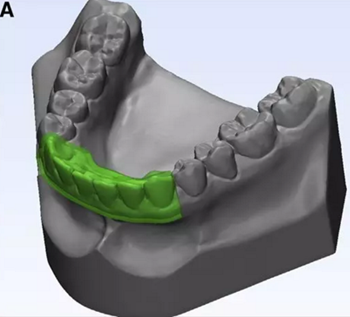

使用體內軟件,第一次融合包括咬合導板在下頜牙齒上定位(圖7)。 圖8顯示了咬合導板和下頜骨(類似咬合導板/游離下頜骨)的完整定位。第二次融合涉及咬合導板的上頜牙齒與顱骨上的的上頜牙齒的定位(圖9)。除了原始的下頜骨最小牙尖分離的3D模型(圖10)之外,這將產生一個構建好的下頜骨完全咬合的3D模型。

圖7. 咬合導板在從模型上修剪下的下頜骨上的定位程序。